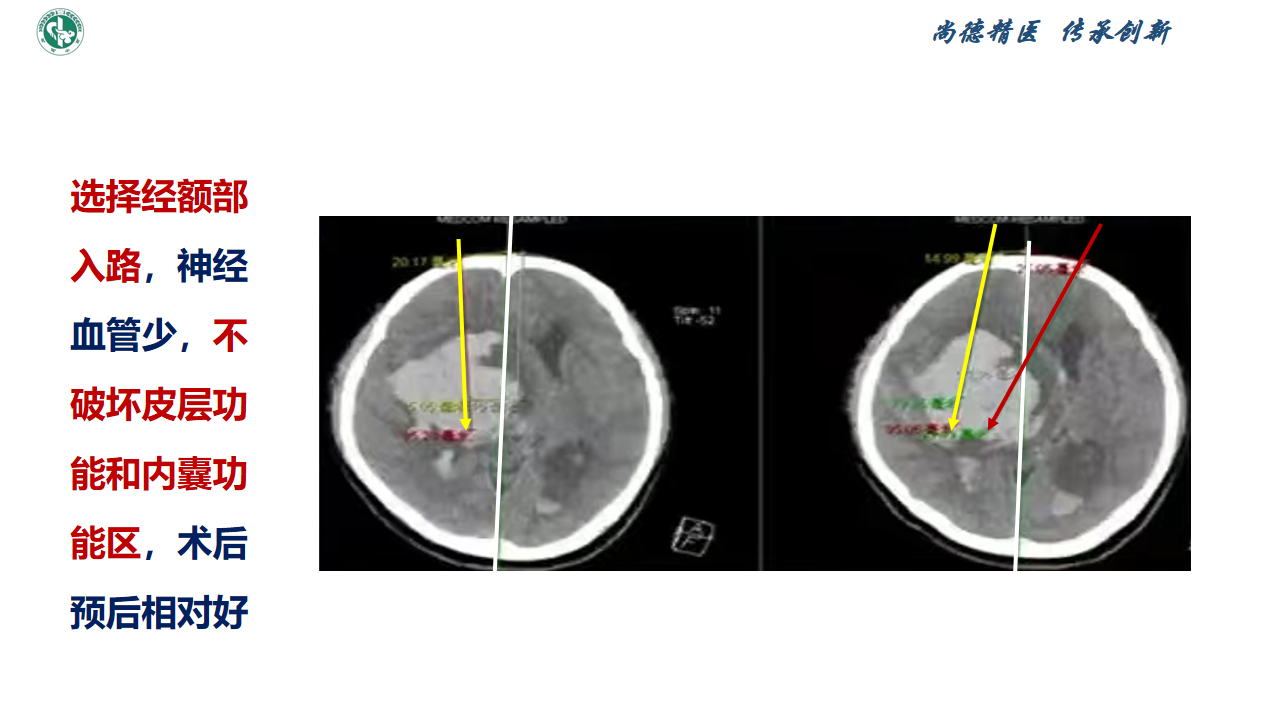

新技术|脑出血微创锥颅软通道引流理念

赵宝元

武威市中医医院